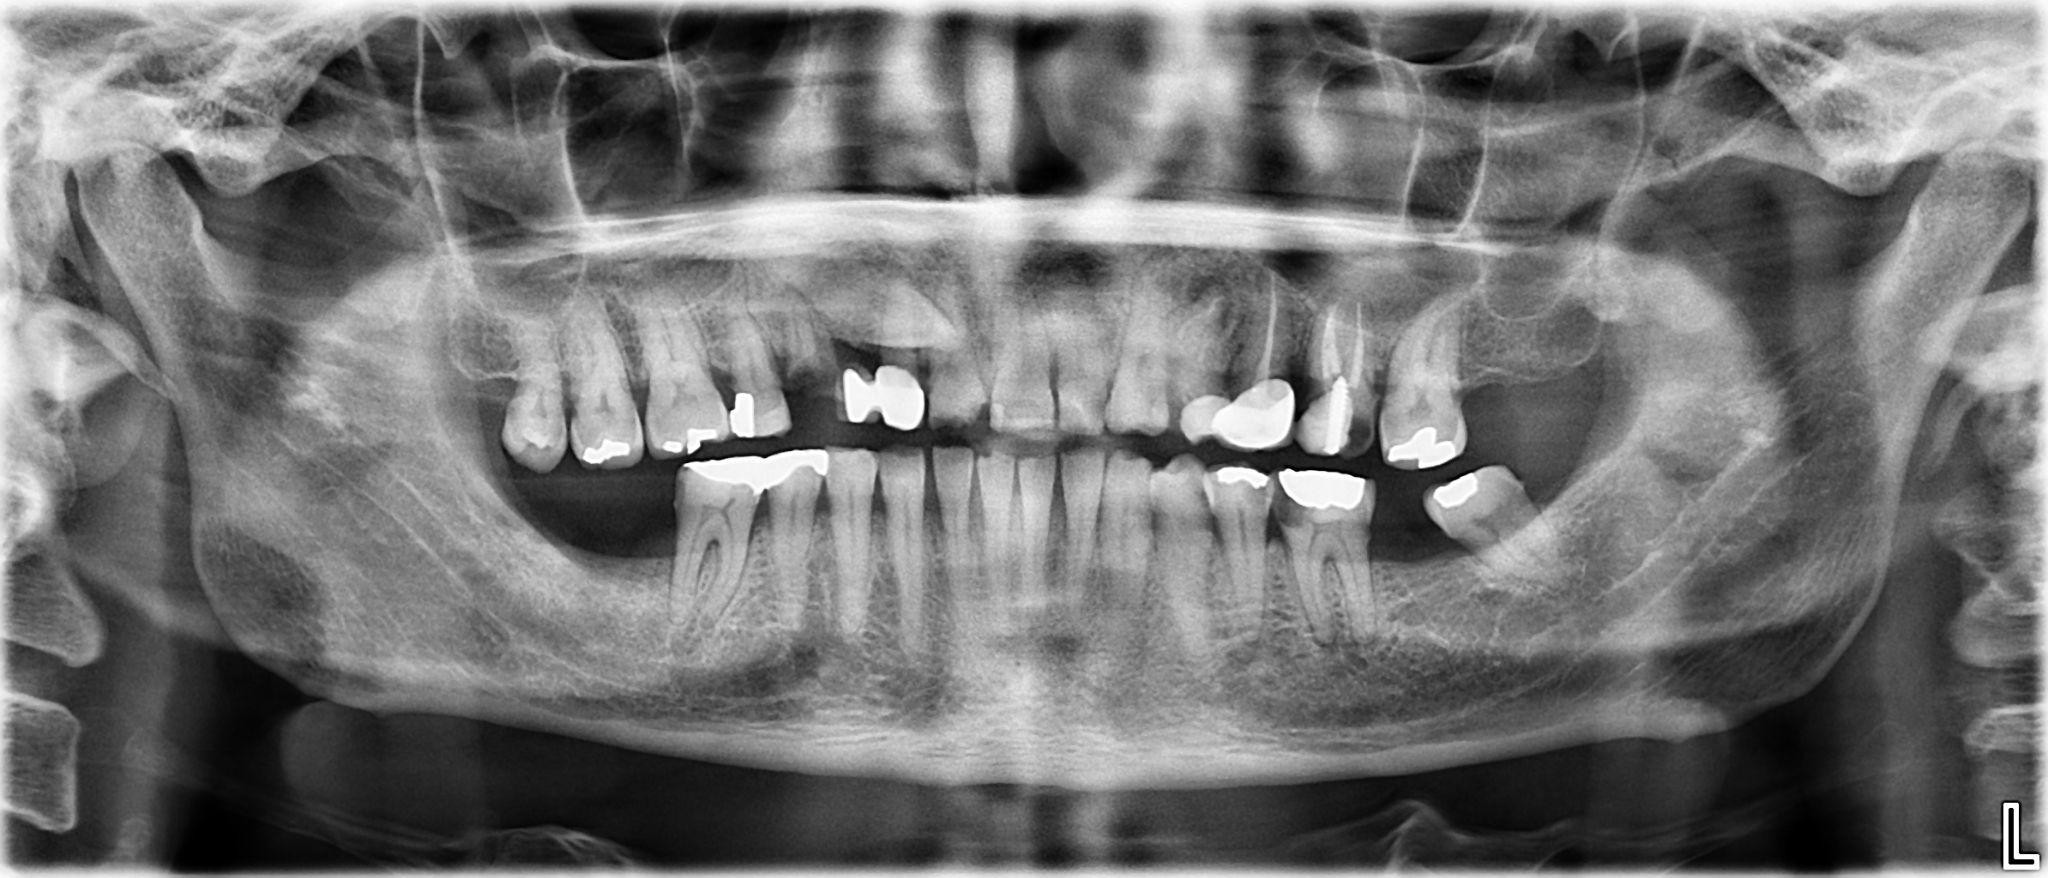

13. What options cannot be selected for the first quadrant of this panoramic X ray?

14. What options cannot be selected for the second quadrant of this panoramic X ray?

15. What options cannot be selected for the third quadrant of this panoramic X ray?

16. What options can be selected for the forth quadrant of this panoramic X ray?

17. What options can be selected for the first quadrant of this panoramic X ray?

18. What options can be selected for the second quadrant of this panoramic X ray?

19. What options can be selected for the third quadrant of this panoramic X ray?

20. What options cannot be selected for the forth quadrant of this panoramic X ray?

21. What options can be selected for the first quadrant of this panoramic X ray?

22. What options cannot be selected for the second quadrant of this panoramic X ray?

23. What options can be selected for the third quadrant of this panoramic X ray?

24. What options can be selected for the forth quadrant of this panoramic X ray?